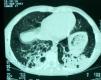

Un niño de 12 años de edad, que tenía diversos animales en su casa, entre ellos palomas, acudió al servicio de urgencias por un cuadro de fiebre elevada, estertores crepitantes e intensa dificultad respiratoria. Presentaba una historia, de 3 meses de evolución, de tos seca, disnea progresiva y adelgazamiento. La analítica mostró 14.470 leucocitos (un 83,5% neutrófilos, un 11% linfocitos y un 0,6% eosinófilos) y proteína C reactiva de 2,28mg/dl. La radiografía de tórax mostró un infiltrado reticulonodular difuso y bilateral. Se inició tratamiento con ceftriaxona, claritromicina y prednisolona. La tomografía computarizada de alta resolución mostró un patrón intersticial bilateral de distribución difusa, con múltiples regiones de hiperdensidad con patrón centrolobulillar y algunas otras en “vidrio esmerilado” (fig. 1). Se observó linfocitosis (82%) en el líquido del lavado broncoalveolar, así como un cociente CD4/CD8 inferior al 1%. Las pruebas de función pulmonar revelaron una capacidad vital forzada (FVC) del 79,5% del valor predicho, un volumen espiratorio forzado en el primer segundo (FEV1) del 70% del predicho y un cociente FEV1 /FVC del 74%. La capacidad de difusión del monóxido de carbono mostró un déficit moderado de la capacidad de difusión.